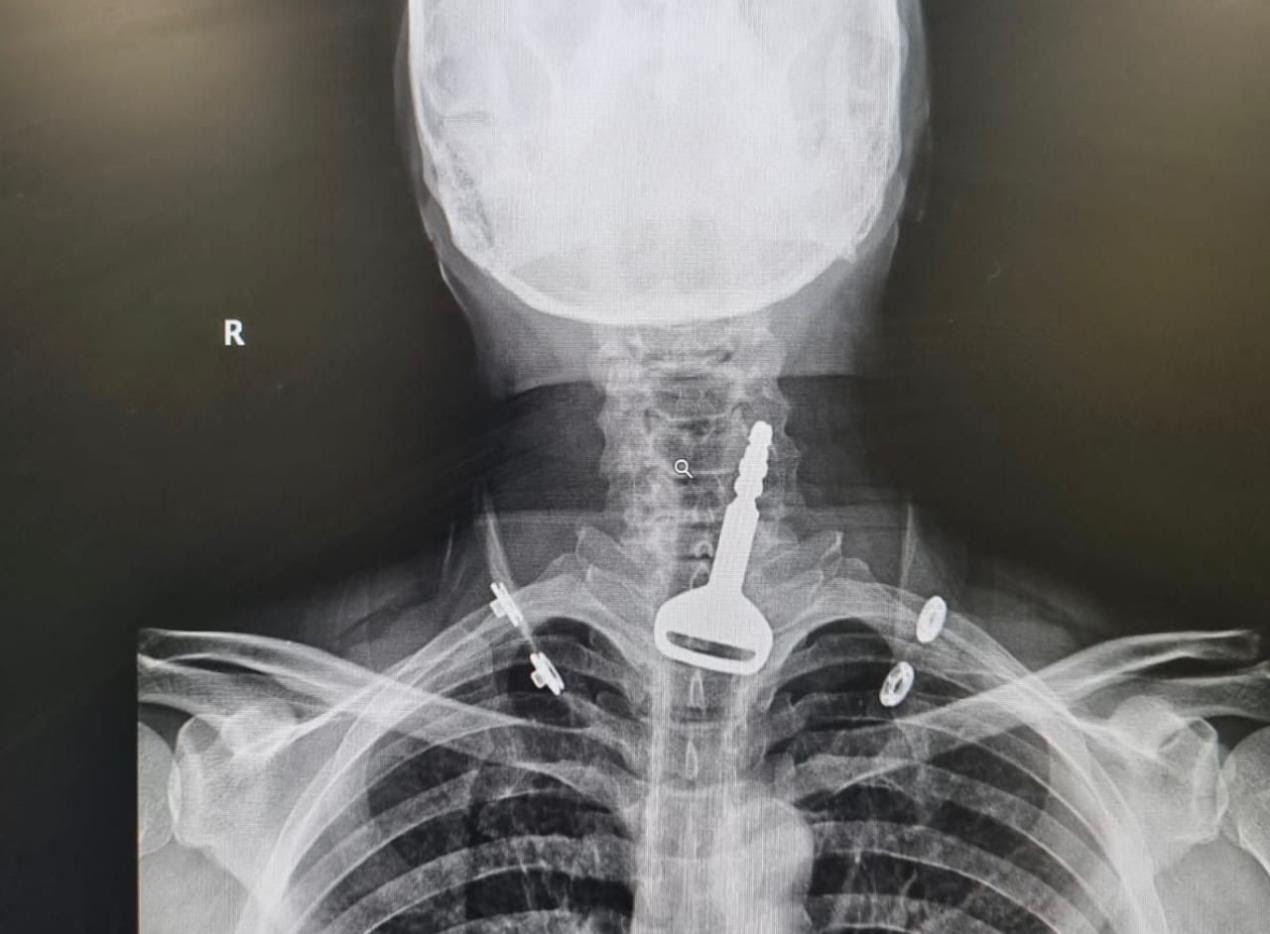

نجح فريق طبي بمدينة القنفذة (غرب السعودية) من استخراج مفتاح سيارة عالق بالجهاز التنفسي لمريض اربعيني كاد أن يودي بحياته، في عملية سريعة استغرقت 15 دقيقة عن طريق المنظار.

وأكدت الصحة السعودية أن الفرق الطبية تمكنت الثلاثاء 11 يوليو من إنقاذ حياة مريض يبلغ من العمر 49 عاما وصل لقسم الطوارئ وهو يعاني من انسداد بمجرى التنفس، حيث اتضح بعد إجراء الفحص السريري والأشعة وجود مفتاح سيارة عالق في القصبة الهوائية.

المريض الذي اعترف للأطباء بأنه كان يلهو بالمفتاح في فمه، ابتلعه عن طريق الخطأ، مما تسبب له في حالة اختناق جزئي، تطلبت التدخل الجراحي عن طريق المنظار لاستخراج الجسم المعدني العالق. ويخضع المريض الذي اتضح أنه يعاني من أمراض في القلب بقسم التنويم لحين استقرار حالته الصحية وخروجه لإكمال فترة النقاهة بمنزله.